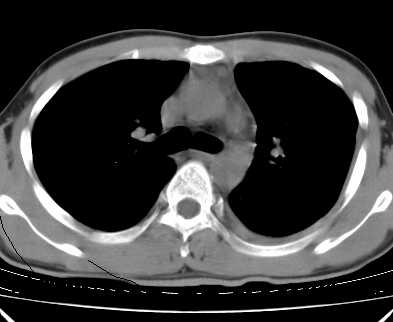

考虑:1、左下肺结核左侧胸腔中量积液,心包积液纵隔肿大淋巴结.

2、心包积液。

心包积液没有,纵隔积液。

1.考虑:左肺化脓性炎症。2.左侧胸腔积液(中等量)。3.心包炎症。

炎性病变为主伴有肺的膨胀不全,伴胸腔积液.心包积液不好定建议超声纵隔淋巴结没看出.